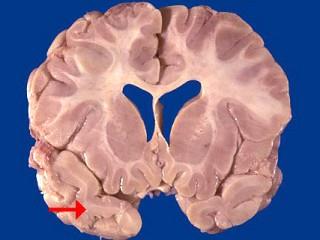

如图箭头所示为大脑哪个部位 ( )A、顶叶B、岛叶C、颞叶D、枕叶E、额叶一、单项选择题

问题 如图箭头所示为大脑哪个部位 ( )

选项 A、顶叶 B、岛叶 C、颞叶 D、枕叶 E、额叶 一、单项选择题

答案 C